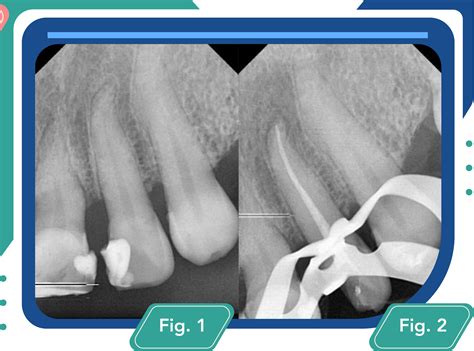

- Diagnóstico y Preparación del Paciente: Empieza por el diagnóstico y la preparación del paciente (bioseguridad y anestesia). Para determinar que un diente debe ser tratado con una endodoncia, es indispensable hacer un diagnóstico preciso. La primera prueba necesaria es un estudio radiográfico, para ver el estado del diente en toda su extensión. Si la afección del nervio no es del todo clara en la radiografía, entonces se procede a valorar la vitalidad del diente.

Radiografía dental para diagnóstico de endodoncia. - Preparación de la Corona y Aislamiento Absoluto: A continuación, procede a preparar la corona y realizar el aislamiento absoluto con diques de goma. Acto seguido, una vez que se ha realizado el saneado de la caries de la pieza a tratar, se realiza un aislamiento con un dique de goma y su respectivo clamp, dejando aislada únicamente la pieza a tratar. Se procede al aislamiento absoluto del diente a tratar. Este aislamiento se lleva a cabo con un dique de goma de látex, que es sostenido al diente con un clamp (grapa) metálico. Una endodoncia sin aislamiento absoluto, acabará en fracaso y pérdida del diente, ya que el contacto con la cavidad oral durante el tratamiento, impedirá la desinfección absoluta del interior del mismo.

Acceso a la cámara pulpar durante la endodoncia. - Localización del Conducto y Longitud de Trabajo: Cuando localices el conducto y obtengas la longitud de trabajo en forma radiográfica y electrónica. En este paso, mediante el uso de un dispositivo digital denominado localizador apical, el dentista especialista en endodoncia determina el tamaño del diente. Determinación de la longitud de trabajo. Antiguamente este procedimiento era muy complejo, ya que el endodoncista solo contaba con la visualización radiográfica del ápice radicular y en algunos casos, era necesario hacer muchas radiografías para dar con la medida adecuada. Hoy en día este dispositivo electrónico, permite alcanzar dicho objetivo, sin la necesidad de tener que llevar a cabo ninguna radiografía.